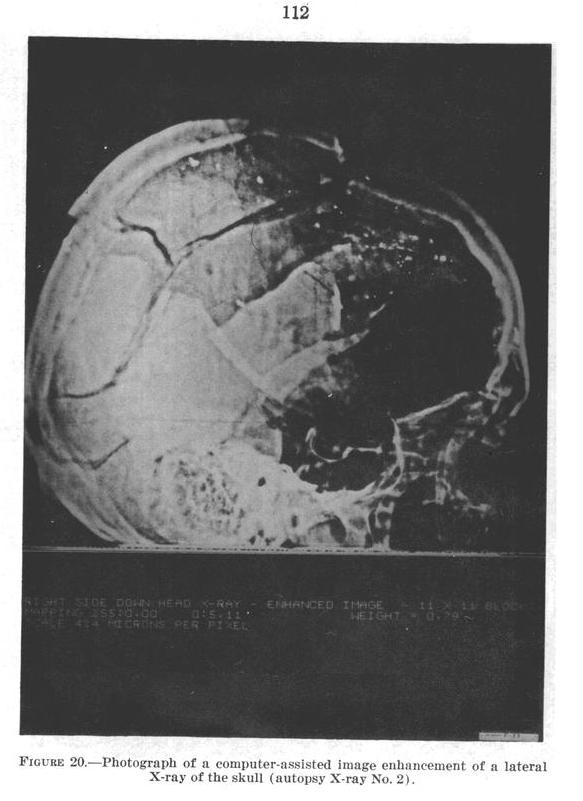

HSCA Appendix Volume 7

Figure 20, Page 112

Oswald Theorists claim that there is damage to the top-front

of the skull where the alleged rear bullet exited, but

claim that no bullet entered or exited the temple. Contrarily,

compare the left intact temple to the right damaged

temple

in HSCA Figure 19. Also notice the missing

temple bone in HSCA Figure 20. (click X-Rays to enlarge)